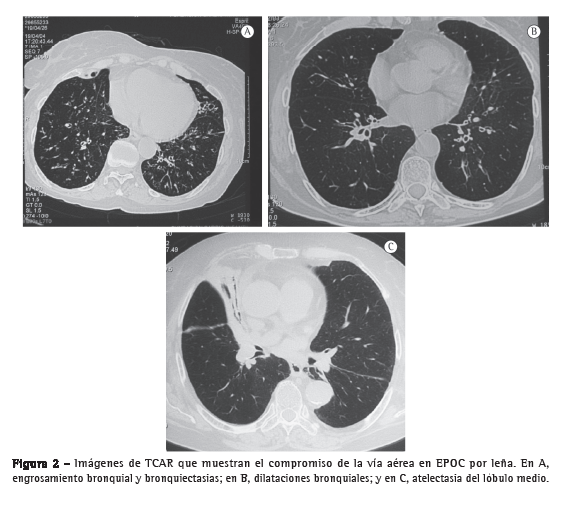

El puntaje de enfisema [mediana (rango intercuartil)] fue significativamente menor en el grupo EPOC-L que en el grupo EPOC-C [0 (0-1) vs. 92,5 (73-103); p < 0,001; Figura 1] y el compromiso de la vía aérea fue significativamente mayor: engrosamiento peribronquiolar (75% vs. 10%; p = 0,008) y dilataciones bronquiales (67% vs. 10%; p = 0,024). Adicionalmente, en las mujeres con EPOC-L se observó la presencia de "árbol en gemación" (25%), atelectasias subsegmentarias (33%) y engrosamiento severo de las paredes de los bronquios mayores que no se encontraron en las mujeres con EPOC-C (Figura 2). En ninguna paciente se observó "patrón en mosaico" en los cortes en espiración. La concordancia entre la lectura inicial y la lectura en consenso para la evaluación del enfisema fue muy buena con un coeficiente de concordancia y correlación de 0,937 (p < 0,001), con una diferencia promedio entre los puntajes obtenidos por los dos métodos de evaluación de 0,030 ± 15,7 y unos límites de acuerdo de Bland y Altman de −30,77 y 30,83.

En este estudio basado en los hallazgos en la TCAR del tórax, demostramos que a diferencia de las mujeres con EPOC-C, las mujeres con EPOC-L y obstrucción severa no tienen enfisema y, por el contrario, tienen un compromiso significativo de la vía aérea manifestado por engrosamiento peribronquial, dilataciones bronquiales y atelectasias subsegmentarias. Estos hallazgos se relacionaron con la menor alteración de la DLCO y de la relación DLCO/VA de las pruebas funcionales encontrada en las mujeres con EPOC-L frente a las mujeres con EPOC-C, hallazgo que se ha descrito en casos de compromiso severo de la vía aérea pequeña con poco enfisema.(10)

Los resultados de la tomografía confirmaron la ausencia de enfisema significativo en las pacientes con EPOC-L y mostraron enfisema moderado en las mujeres con EPOC-C. Estudios previos han demostrado que esta cuantificación subjetiva del enfisema en la TCAR se correlaciona de manera significativa con la extensión del enfisema cuantificada en cortes microscópicos de especímenes resecados.(19,20) Aunque esta cuantificación subjetiva puede tener desventajas como la sobrestimación del grado de enfisema y, en ocasiones, la baja concordancia entre diferentes observadores,(21) consideramos que la técnica empleada en nuestro estudio fue adecuada, teniendo en cuenta las claras diferencias encontradas entre los dos grupos y la buena concordancia entre la lectura individual por los tres lectores y la lectura realizada en consenso, haciendo que nuestros resultados sean altamente reproducibles. Como se anotó, en las mujeres expuestas al humo de la leña, además de la ausencia de enfisema, se encontró engrosamiento peribronquiolar, dilataciones bronquiolares y bronquiales y atelectasias subsegmentarias demostrando un gran compromiso de la vía aérea. La presencia de atelectasias es un hallazgo frecuente en la EPOC-L y se ha relacionado con el hallazgo endoscópico e histológico de antracosis e inflamación bronquial.(9,22)